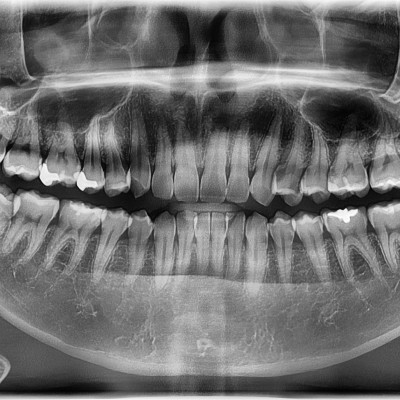

#28,38 사랑니 발치 #28,38 사랑니 발치 구강 외과 전문의가 당일 발치했습니다. --------------------------..

작성자 이턱이 작성일 03-12 조회 41